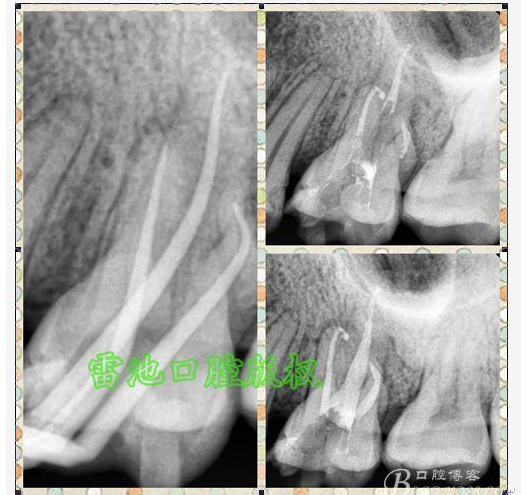

E 、X線影像學的檢查研判能力: 這點不需要強調太多,對于普通的非CBCT的二維影像對醫(yī)生讀片能力有一定的要求,有個逐步提高的過程,非一蹴而就,需要學會把二維的X線影像與三維的解剖結構進行良好的對應結合,對于某些鈣化的髓室底,應通過想象把根管口的分布、根管的走向以及各種變化通過想象投射到對應的髓室底上;

G:找尋MB2的問題:

1、查閱各種文獻,MB2的發(fā)生率在52-96%之間,治療時遺漏是上頜磨牙根管治療失敗的主因,2、一般位于MB1根管口與腭根管口方向的0.5-5mm范圍內,而大多數都位于MB舌側的1-3mm處,其中2mm以內占85.7%,3、MB1-P根管口連線與MB1-MB2根管口的連線夾角大部分(74.3%)在30度以內;4、MB2的尋找大部分需要去除相應部位的牙本質;5、當找到的MB根管口呈“長線型”且有深色凹線向舌側,或者找到的MB根管口明顯偏頰多提示有MB2的可能;6、DOM(牙科手術顯微鏡)的使用有助于找尋MB2;

H、關于下磨牙MM根管的重視問題: